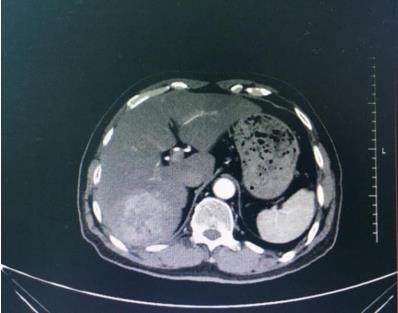

梁某某,男性,70歲,發(fā)現(xiàn)肝臟占位病變3天,既往有乙肝病史20余年。甲胎蛋白3302 UL/mL,臨床診斷肝右葉(S67)肝癌。

肝右葉(S67)肝癌,緊鄰下腔靜脈。

該患者腫瘤位置緊鄰下腔靜脈,手術(shù)風(fēng)險(xiǎn)極大;需切除右半肝才能完整切除腫瘤,而右半肝體積占全肝體積的65 %;如此大范圍的肝切除,面臨術(shù)后肝功能衰竭的風(fēng)險(xiǎn)。